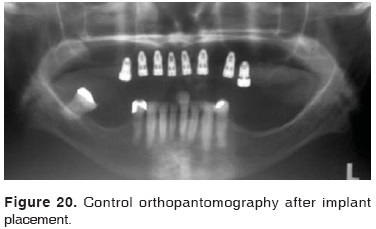

The patient experienced a post-operative period free of intra oral iliac crest wound complications; therefore, a temporary prosthesis was placed with tissue conditioner (Figure 17). Six months later, a sufficiently long and thick alveolar process was obtained (Figure 18), which allowed placement of eight intra-osseous implants (Figures 19 and 20). A full fixed prosthesis was placed, which was supported by zirconium-ceramic implants. During a four year evolution period, in the long term, the alveolar process was reconstructed to reach suitable width and length; therefore, surgical aims as well as patient's expectations were met (Figures 21 to 23) (22).